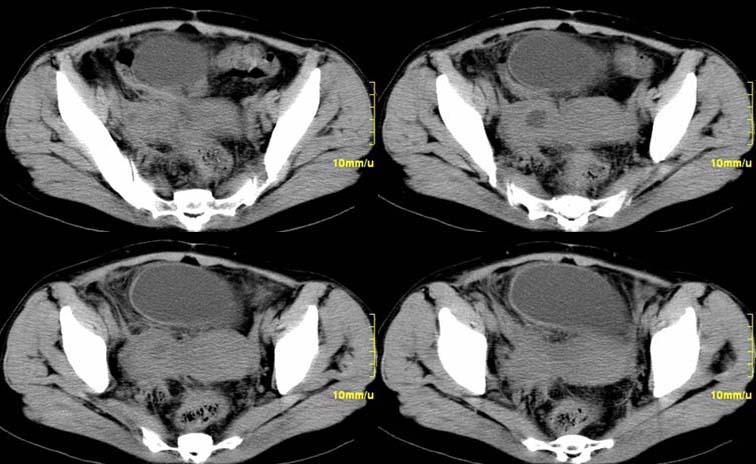

患者,52,右下腹疼痛一月,当时有发热,抗炎治疗20余天,至今仍疼痛,且有低热。

增强

右附件区软组织包块,内囊变坏死,边缘模糊,与子宫,与膀胱分界不清,增强强化与子宫密度相近.盆腔内无肿大淋巴结考虑炎性包块可能性大。

右附件区软组织包块,内可见坏死,边界不清,周围软组织及脂肪组织可见密度增高,膀胱右侧壁增厚,并且呈膨胀不全的改变,考虑炎性包裹,不知道有没有手术史??

临床特点:

右下腹疼痛一月,当时有发热,抗炎治疗20余天,至今仍疼痛,且有低热,具有典型炎症的临床表现。

ct表现:

右侧附件见一肿块,边缘与周围组织分界不清,增强扫描见肿块明显强化,越到后期强化越明显,中央见坏死,内壁光整,与临近子宫壁、直肠及膀胱后壁均见炎症波及。这种厚壁肿块、内缘光整外缘模糊、增强扫描强化越后越强是附件脓肿典型的ct表现。

诊断:

右侧卵巢输卵管慢性脓肿,炎症波及临近子宫、直肠及膀胱形成粘连。